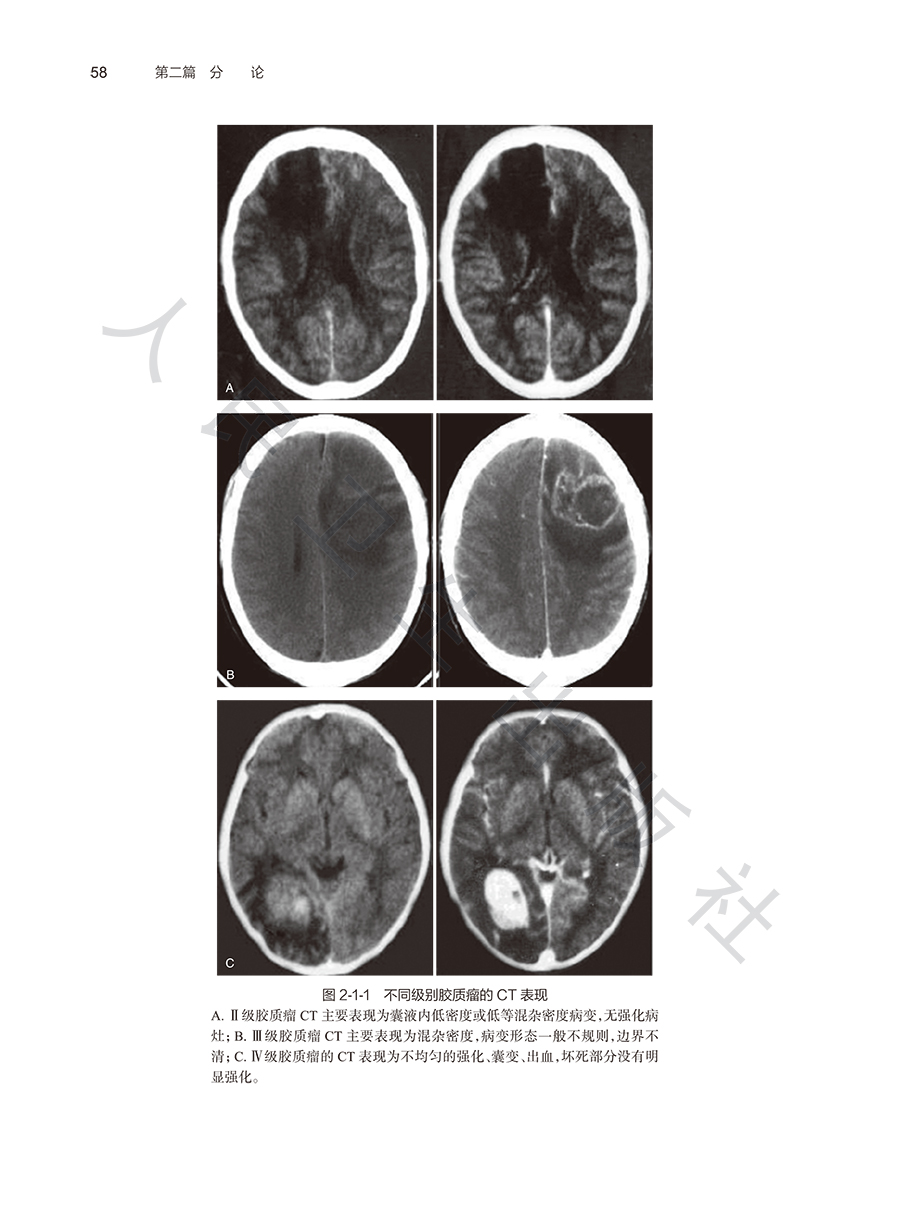

本书一共分为2章,“总论”与“各系统常见恶性肿瘤”。“总论”部分具体包含了肿瘤的流行病学,健康管理在肿瘤心理学、肿瘤营养学中的应用。“各系统常见恶性肿瘤”部分包含肺癌、结直肠癌、肝癌、食管癌、胃癌、乳腺癌、子宫颈癌、鼻咽癌和前列腺癌等,每个癌种分别从流行病学现状与危险因素、常见筛查与早诊方法、随访策略与健康管理等方面进行了阐述。按照不同系统,选取我国发病率较高或预后较差的癌种,结合实际的癌症筛查工作的经验及研究成果,提出相关的规范化的筛查路径及程序,实用强性强,获益大且覆盖范围广泛。